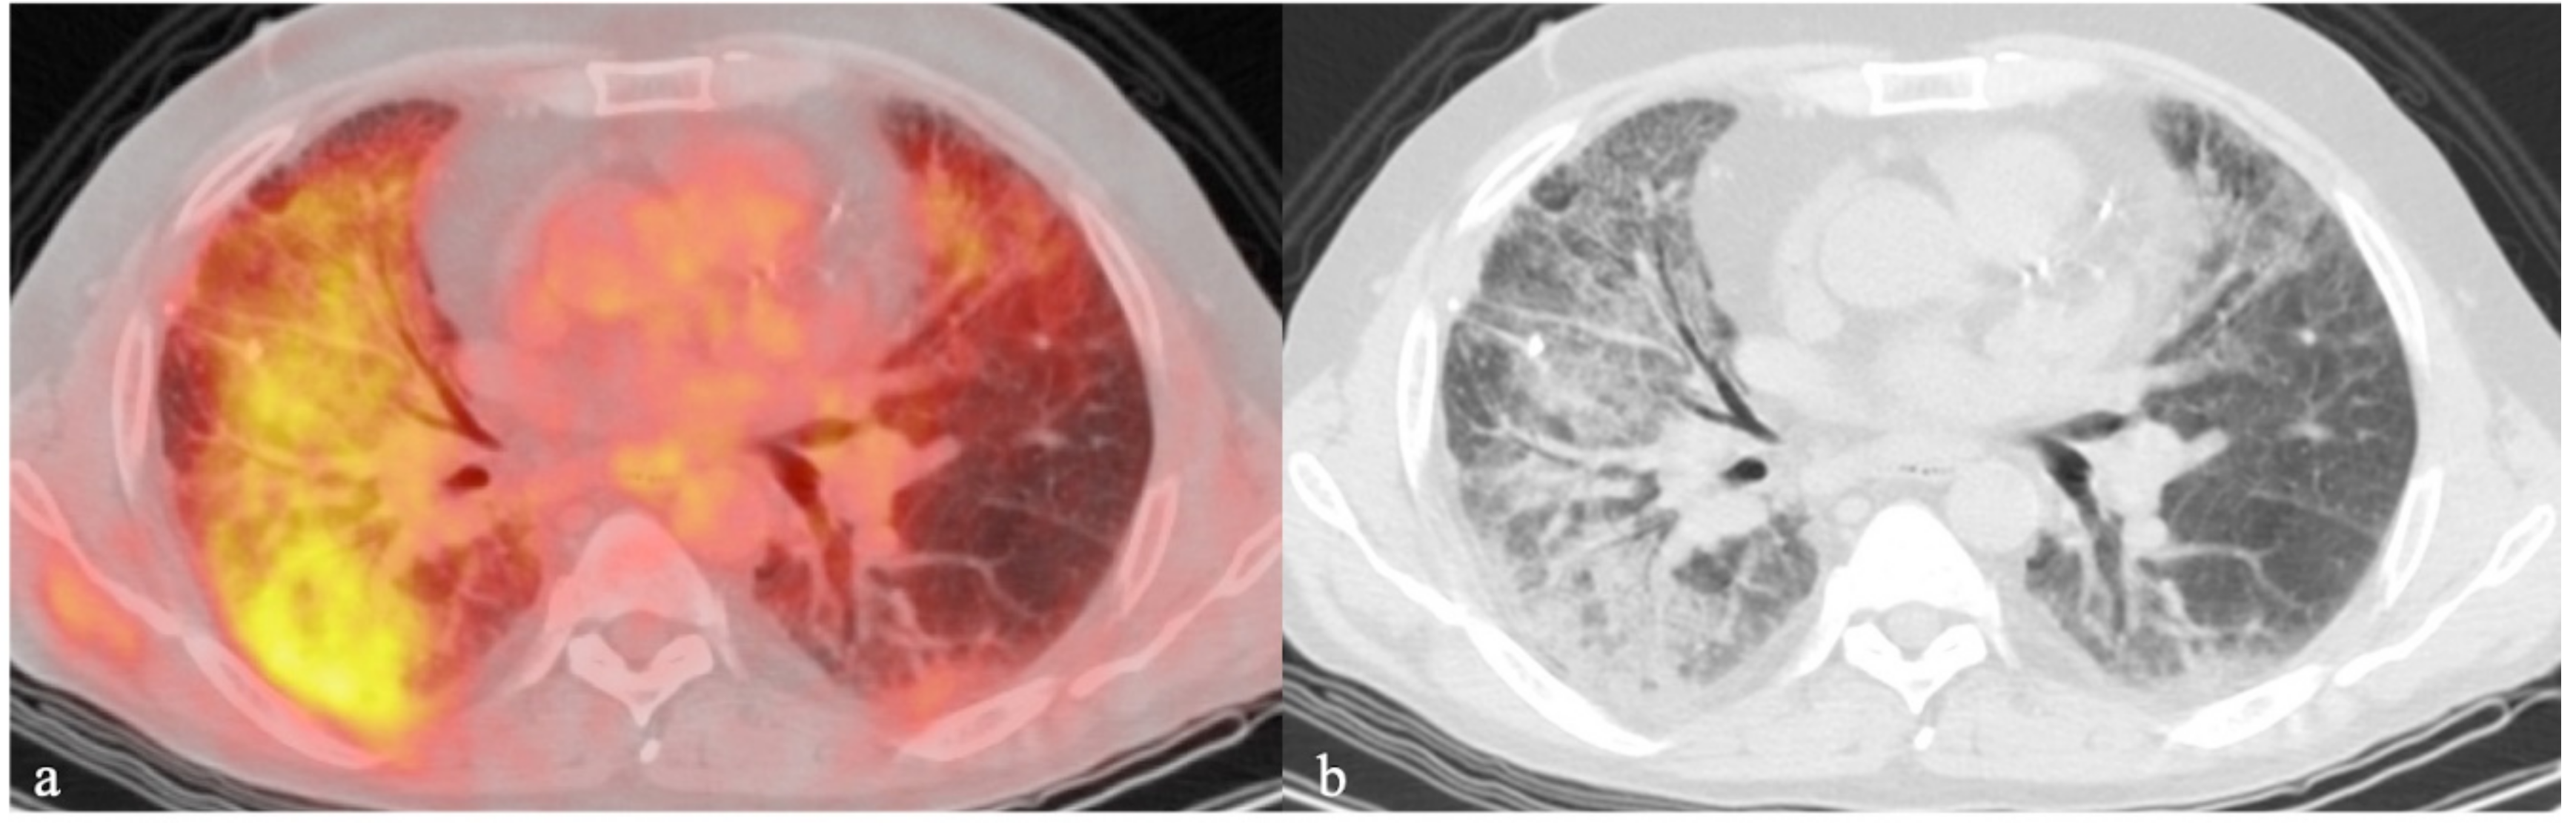

- Thomas, B.A.; Molton, J.S.; Leek, F.; Pang, Y.; Totman, J.J.; Paton, N.I.; Townsend, D.W. A comparison of 18F-FDG PET/MR with PET/CT in pulmonary tuberculosis. Nucl. Med. Commun. 2017, 38, 971–978. [Google Scholar] [CrossRef] [PubMed]